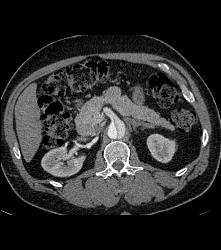

Occluded Right Common Iliac Artery